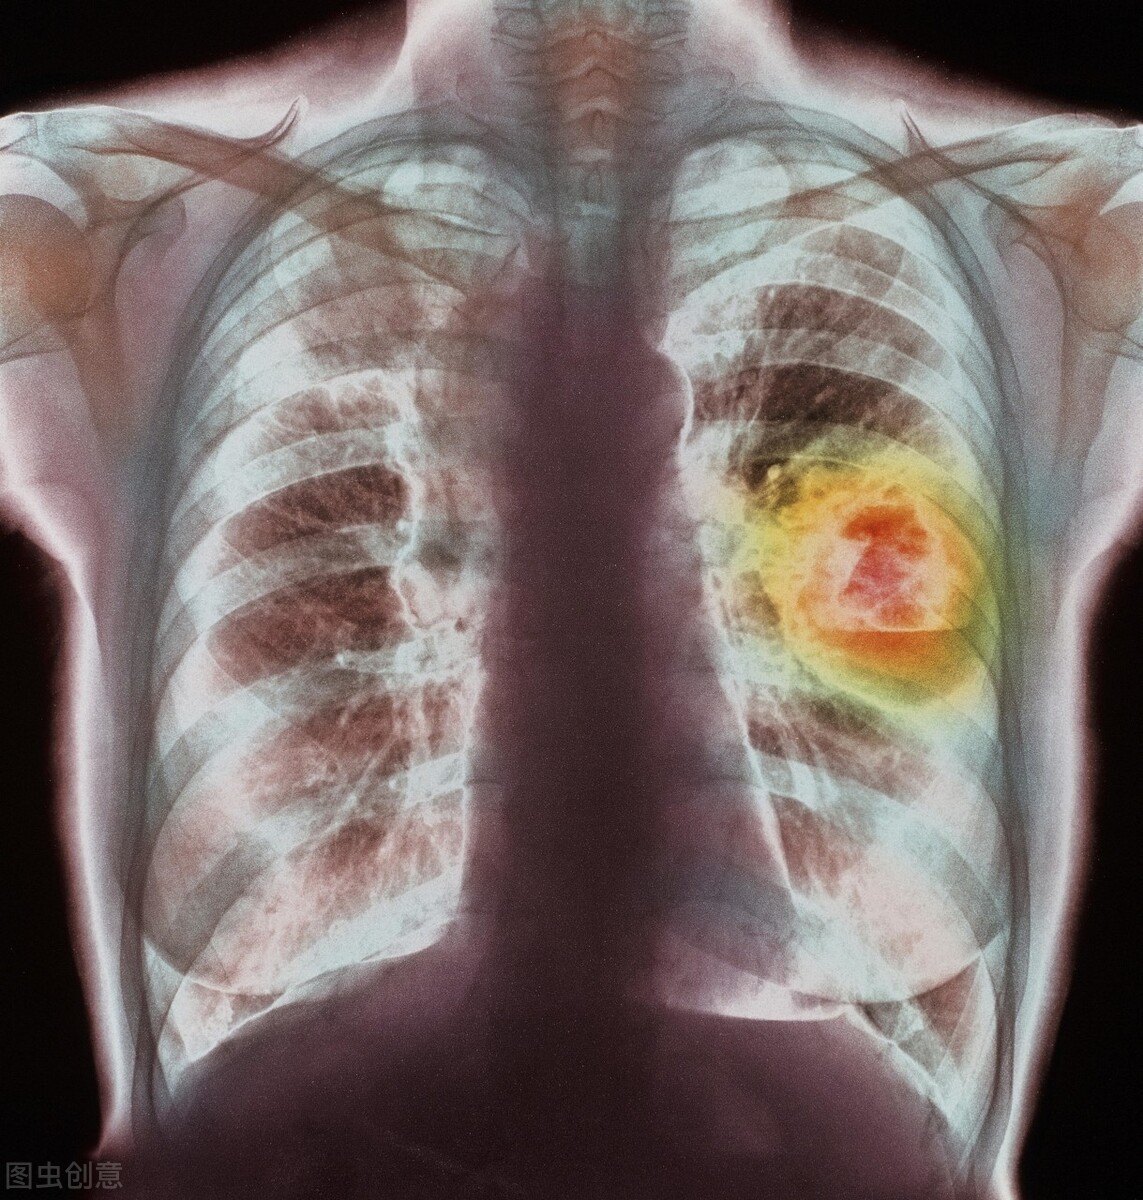

Liver cancer is one of the most common solid malignant tumors clinically. Due to its insidious onset, rapid progression, high malignancy, tendency for metastasis and recurrence, short survival period, and difficulty in treatment, it is a disease with high mortality rates worldwide. Currently, the primary treatment for liver cancer remains surgery, and 40% of liver cancer patients can benefit from surgical treatment. However, a significant number of patients are unable to undergo surgical resection due to various reasons such as physical condition, liver function, tumor location and size, cirrhosis, severe jaundice, or ascites. Additionally, the recurrence rate among patients treated with surgical resection is approximately 40%-60%. Invasive treatment methods have yet to effectively combat liver cancer, and currently used anti-cancer chemotherapy drugs have not achieved the expected efficacy. At the same time, any radiotherapy or chemotherapy regimen is accompanied by significant toxic side effects, leading many patients to discontinue and abandon treatment. Traditional Chinese medicine (TCM) syndrome differentiation and treatment, while demonstrating certain efficacy and unique advantages in the treatment of liver cancer, faces challenges due to the complex and variable pathogenesis and clinical manifestations of the disease. Syndrome differentiation and treatment represent the theoretical core of TCM.